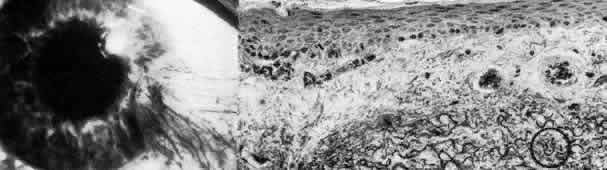

The appellation of map-dot-fingerprint dystrophy is appropriately descriptive of the biomicroscopically visible features of intraepithelial microcysts (dots), subepithelial ridges (fingerprints), and geographic opacities (maps) (Fig. 6; Color Plate 1D).49–66 Family studies have revealed a probable dominant inheritance for map-dot-finger-print dystrophy, with variable penetrance.67 Other clinical studies are more consistent with degeneration that is rather highly prevalent in the general population.56

Fig. 6. Map-dot-fingerprint dystrophy. Top left. Clinical photograph of a 37-year-old man with non-traumatic erosions shows characteristics of map dystrophy with superficial geographic haze interrupted by clear areas. Top right. In the dot form of Cogan's mycrocystic dystrophy, superficial, opaque cysts are evident within the epithelium. Upper middle. Three variants of fingerprint dystrophy show subepithelial ridges, particularly enhanced by retroillumination. Lower middle left. Phase-con-trast microscopy of map dystrophy shows fibrous tissue (*) interposed between epithelium and Bowman's layer (B) (paraphenylenediamine, × 1000). Lower middle center. Phase-contrast microscopy of dot dystrophy shows an intraepithelial pseudocyst evolving from disintegration of desquamating cells (paraphenylenediamine, × 1200). Lower middle right. Phase-contrast micrograph of fingerprint dystrophy illustrates fingerlike intraepithelial extensions of aberrant fibrocellular material anterior to the normal-appearing Bowman's layer (B) (paraphenylenediamine, × 800). Bottom. Transmission electron micrograph in these disorders consistently finds multiple laminations of basement membrane material (*) with reduced hemidesmosomes (small circle) and increased anchoring fibrils (large circle) beneath epithelium (E) (× 40,000). (Upper middle, slit lamp photographs courtesy of Lawrence Hirst, MD)

Many ultrastructural studies of map-dot-finger-print dystrophy have disclosed a discontinuous multilaminar, thickened basement membrane under the abnormal epithelium.49,64,65 Sometimes this abnormal basement membrane contains an admixture of collagenous and cellular debris suggestive of prior breakdown episodes. More widespread coalescence of this subepithelial material gives the clinical maplike picture. Other configurations of aberrant basement membrane and fibrillar collagens can be found extending in ridges into the epithelial layers, thereby explaining the fingerprint pattern. Epithelial microcysts are actually pseudo-cystic collections of cellular and amorphous debris within the epithelial layer. Their shape changes with time since they are formed from entrapped cellular material deeper within the epithelium. As they travel to the surface, they may coalesce with other cysts and finally break through the surface, giving rise to an irritative episode.

The primary defect in map-dot-fingerprint dystrophy is presumably the synthesis of abnormal basement membrane and adhesion complexes by the dystrophic epithelium. Unable to form proper hemidesmosomes or anchoring fibrils, the epithelium undergoes recurrent subclinical or overt episodes of dysadhesion. This periodic “lift-off” allows debris to accumulate subepithelially, providing an even less adequate substrate on which the already abnormal basement membrane must form. Moreover, intraepithelial extensions of abnormal basement membrane and collagenous material may block the normal surface migration of maturing epithelial cells, allowing the formation of encysted collections of debris. Thus, the cycle is to a degree self-perpetuating, with primary faulty epithelial adhesion secondarily causing abnormal epithelial maturation which, in turn, exacerbates the accumulation of abnormal basement membrane and collagenous debris and leads to further worsening of epithelial adhesion. Gentle débridement of severely aberrant epithelium and, in some instances, superficial keratectomy to remove subepithelial debris is an aid to conservative therapy with lubricants, hypertonic saline ointment, patching, or bandage soft contact lens.